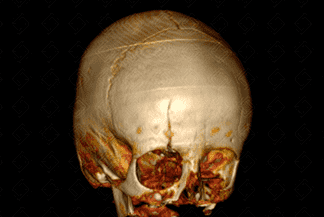

Texto alternativo para a imagem Figura 3. Créditos: Dra Elazir Mota - Rio de Janeiro/RJ

Descrição da lesão: Traumatismo cranioencefálico na criança. Tomografia computadorizada do crânio com reconstrução tridimensional (3D): presença de volumoso hematoma subgaleal na região frontal direita (figura 1, setas vermelhas). Na reconstrução tridimensional, nota-se o traço de fratura na mesma topografia com extensão ao teto da órbita deste lado, sem desalinhamento ósseo significativo (figura 2 e 3).